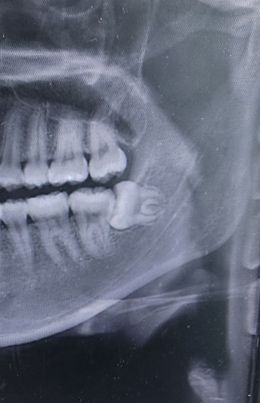

사랑니때문에 저저번주에 잇몸이 부어서 아팠고, 저번주까지도 음식물씹는데 좀 불편한감이 있었는데 이번주에는 음식물씹어도 괜찮고 아픈게 사라졌습니다 근데 치과에서 아팠을때 갔었는데 아프면 발치해야되는데 대학병원을 가보라고 했어서 오늘 가려고 하는데 또 아픈게 싹 사라져서 안가도 될지 문의드립니다 부모님께서는 오늘 가서 발치를 하는게 아니라 검사를 하는거고 발치하려면 세네달 후에나 가능하다고 해서 의사소견이라도 듣자고 하십니다 이가 사진과 같이 가로로 누워있는 상태입니다 그리고 고3이라서 10월 말부터 11월초부터 면접이라 그때 아프면 안되긴합니다..수능은 최저없어서 상관없고요

가로로 누워있는 매복사랑니의 경우 앞의 어금니를 상하게 하고, 통증 및 붓기를 지속적으로 유발하게 됩니다. 이 경우에는 빠른시일내에 발치를 하는 것이 좋기에 미리 검사를 받고 바로 발치가 필요한 상황인지 확인을 해보길 권합니다.